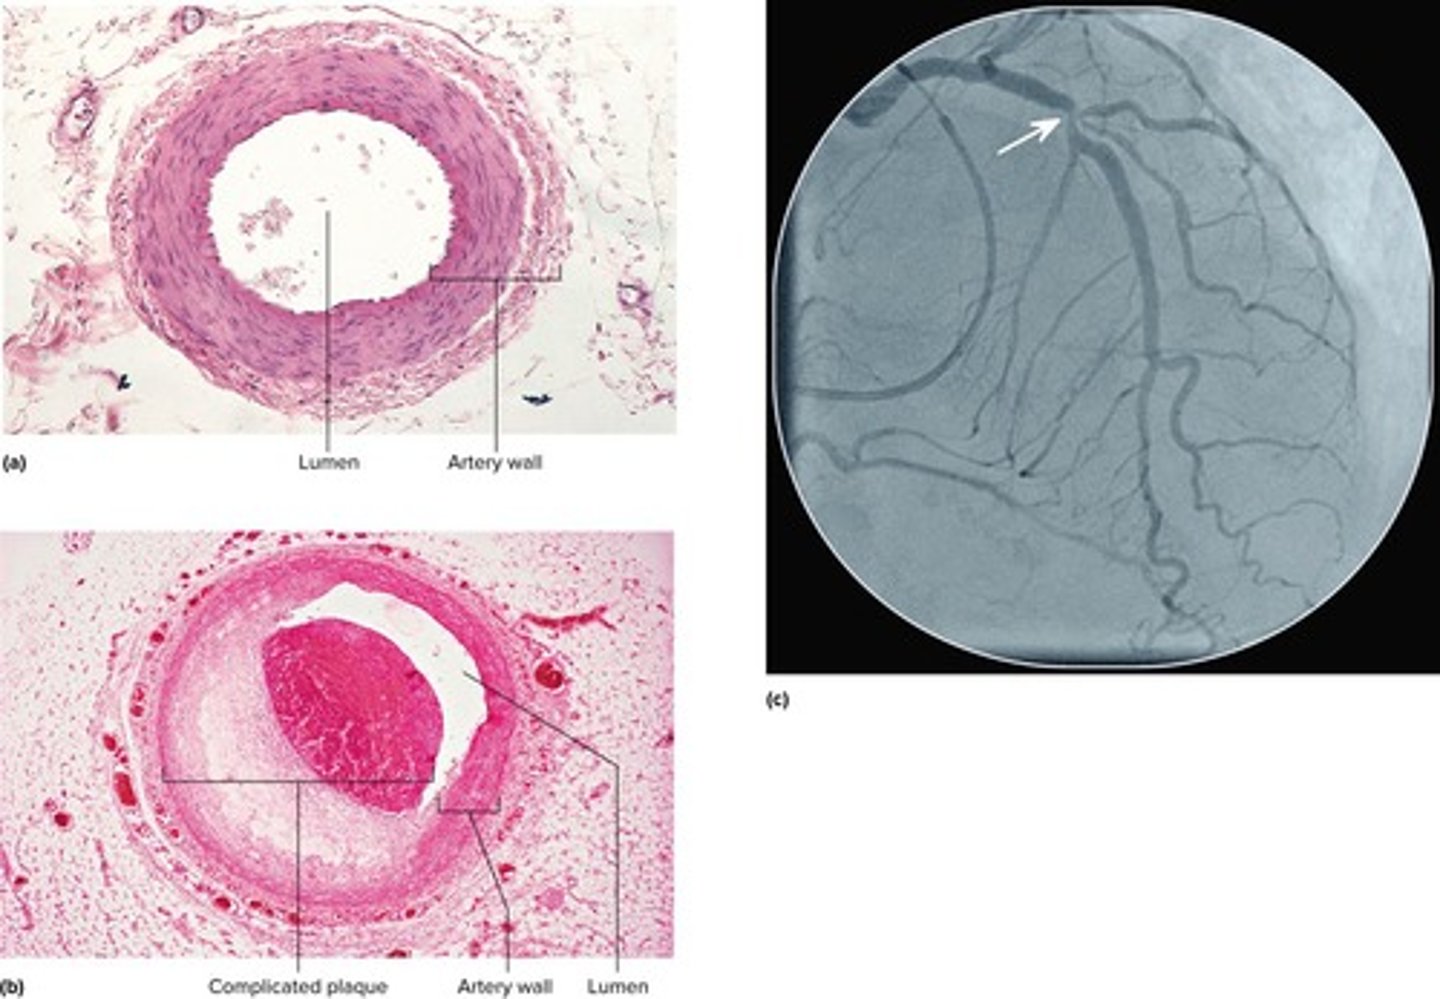

What is coronary artery disease (CAD)?

A constriction of the coronary arteries, usually due to atherosclerosis.

What is angina pectoris?

Chest pain from partial obstruction of coronary blood flow.

What is a myocardial infarction (MI)?

Sudden death of a patch of myocardium resulting from long-term obstruction of coronary circulation.

To supply blood to the heart muscle itself.